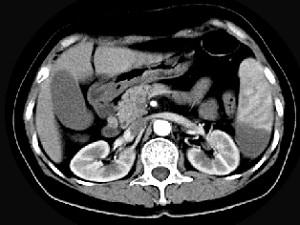

女、54岁,左上腹痛,CT检查如图,最可能的诊断是 ( )A、脾血管瘤B、脾转移瘤C、脾脓肿D、脾梗死E、脾淋巴瘤

问题 女、54岁,左上腹痛,CT检查如图,最可能的诊断是 ( )

选项 A、脾血管瘤 B、脾转移瘤 C、脾脓肿 D、脾梗死 E、脾淋巴瘤

答案 D